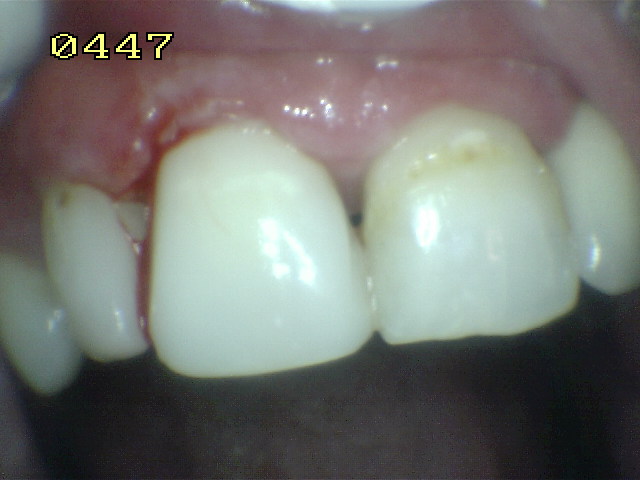

| Lavar, secar y

observar si textura se encuentra libre de poros |

Caso

terminado |